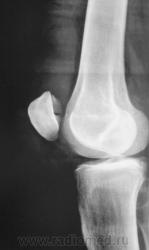

перелом надколенника( редко такой встречается) препателярная гемабурса, гемартроз, сильно пострадала суставная поверхность надколенника

Наверно все таки пателля бипартита. Представить, чтобы так красиво и ровно откололось - трудно... А мягкотканный компонент знатный...

Сам думал о "бипарцита", кстати, недавно был случай с "трипарцита". Но в данном случае был в растерянности, клиника "зашкаливает", конечно, возможно из-за мягкотканного компонента.

В минус травме говорит такая "красивенькая форма" отломка? НО при бипарите про мягкотканный компонент я данных ненашел..